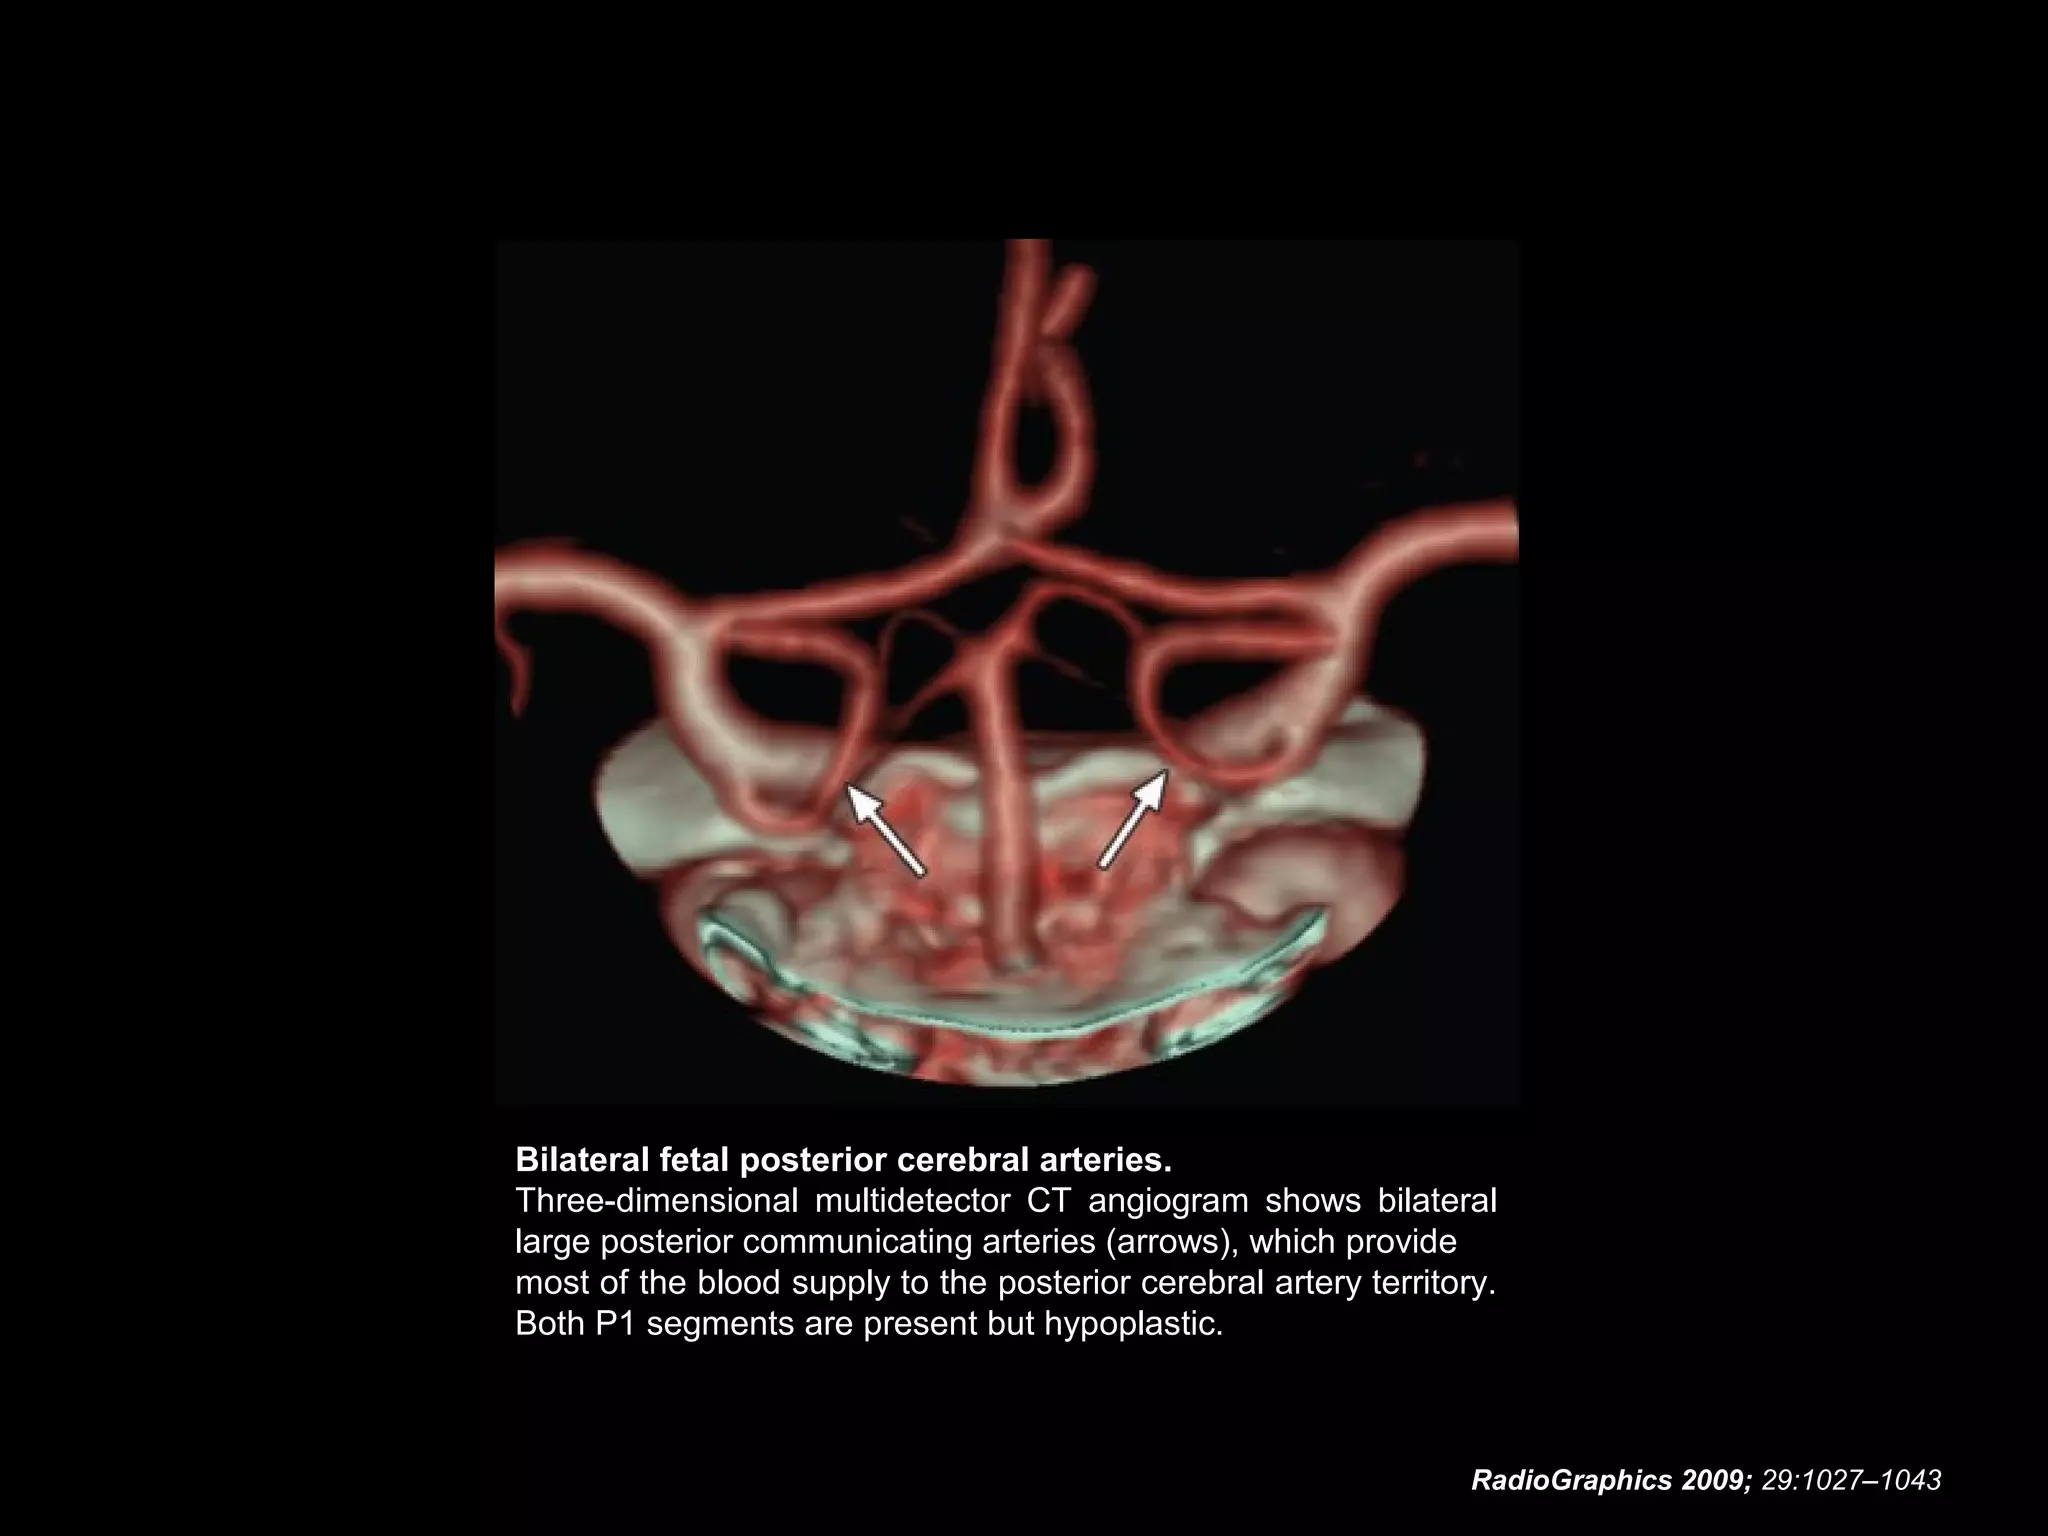

Fetal Origin of the Posterior

Cerebral Artery

• In the presence of this anomaly, the caliber of the

posterior communicating artery may be the same as or

greater than that of the ipsilateral P1 segment, and the

dominant blood supply to the occipital lobes comes from

the internal carotid artery.

• Fetal origin of the posterior cerebral artery occurs when

the embryonic posterior cerebral artery fails to regress.

• It may occur on the right side (10% of the general

population), the left side (10% of the general population),

or bilaterally (8% of the general population).

• The P1 segment may be absent in fetal origin of the

posterior cerebral artery, but its absence is an

uncommon finding.

RadioGraphics 2009; 29:1027–1043

Bilateral fetal posterior cerebral arteries.

Three-dimensional multidetector CT angiogram shows bilateral

large posterior communicating arteries (arrows), which provide

most of the blood supply to the posterior cerebral artery territory.

Both P1 segments are present but hypoplastic.